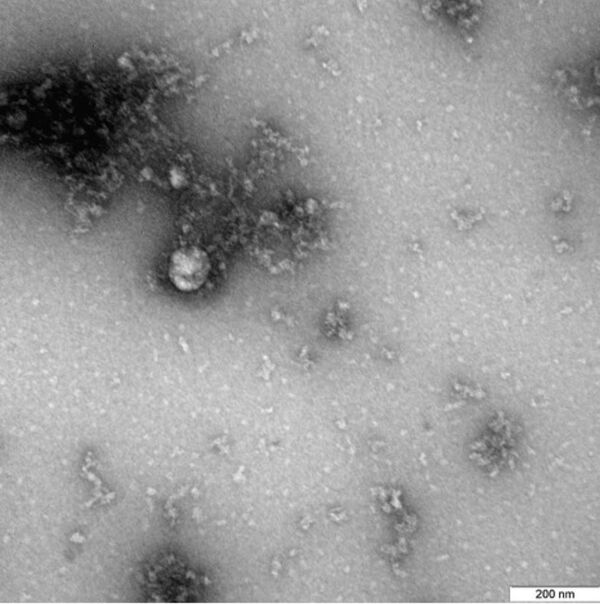

ЕРЕВАН, 25 янв - Sputnik. В России представили первый в мире снимок британского штамма коронавируса, сообщается на сайте Роспотребнадзора.

"Данный снимок британского штамма коронавируса был выделен от пациента в декабре 2020 года", - говорится в публикации.

Фотография вируса под микроскопом получена в рамках продолжающегося изучения свойств данного варианта нового коронавируса, включая его структурные особенности и проявления в клеточных культурах и экспериментальных моделях с использованием лабораторных животных.